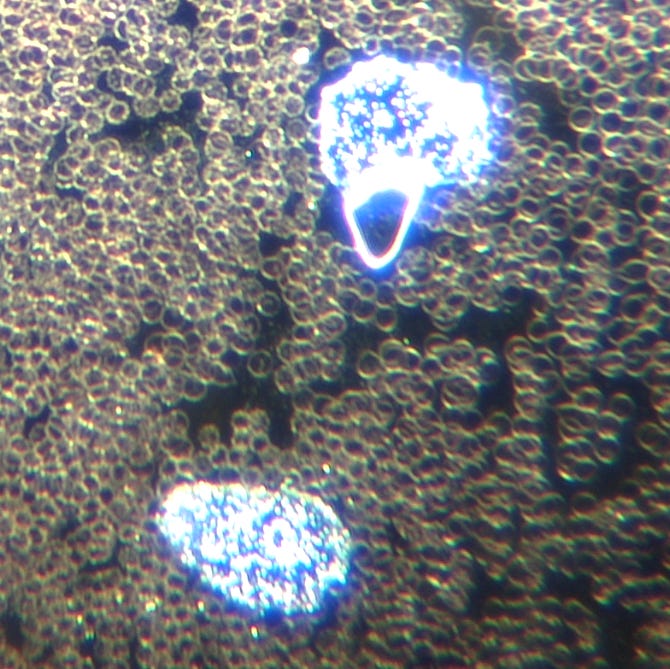

Mariano du club Tzla m'a envoyé cette image microscopique d'une micropuce extraite de la peau après utilisation de la machine Tzla.

Image : Puce électronique d’une personne non vaccinée contre la COVID-19, sortie avec l’appareil de traitement au plasma. Image prise avec le mode macro de l’appareil photo d’un smartphone fixé au microscope. Grossissement : 120x.